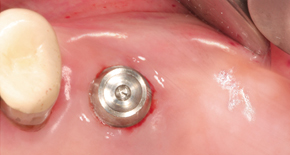

2. No incision, Minimal implant hole

3. Placing MagiCore